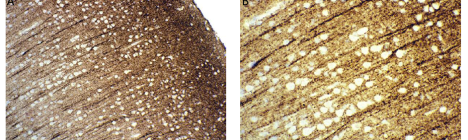

Infantile Tauopathies: Changing How We Think of Neurodegeneration

When we think of the term, “neurodegeneration,” the classic pictures of Alzheimer’s or Parkinson’s Diseases typically come to mind. We may envision an older person who exhibits memory loss, maybe […]